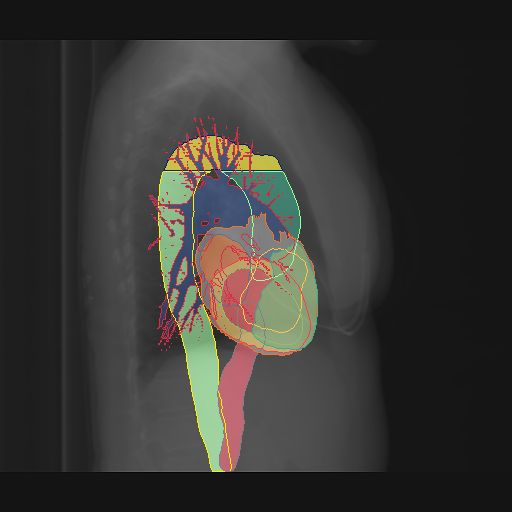

We display qualitative results in Fig. 3. The annotators tend to be content with most annotations. There are edits at the extensions of the esophagus, trachea, and aorta and corrections of the lower ribs. There is little consensus for classes in the abdominal area, such as the stomach, as seen on the right of Fig. 3 . In contrast, the annotators often align for bone classes.

We show the quantitative segmentation performance against medical expert annotations for all classes in Fig. 3 . The dashed lines represent the IAA, whereas the dotted line displays the average MAA. As the task for the human annotators was not to annotate from scratch but to correct wrong pixel-wise predictions, we can see a high MAA for most classes. In the frontal view, the most significant disagreements exist for rare bone structures such as L3 and C4, lower ribs, the mediastinal distribution, or the breast tissue. The IAA and MAA are highly similar with mIoU of respective 95% and 94%. The Hausdorff distance for MAA is slightly lower than the IAA, indicating slight differences in boundary annotations while maintaining a considerable overlap with the other annotator. In the lateral view, the concrete delineation of rib structures appears ambiguous, leading to lower MAA and IAA with a greater IAA than MAA for all metrics in this supercategory. Overall there is less agreement between the medical experts in the lateral view, leading to a better average MAA than IAA across all metrics (i.e. 85% vs 83% mIoU). While the experts propose changes to the original predictions, they are often not overlapping. In the lateral view, rib segmentations can become quite hard to interpret. While both annotators disagree with the rib segmentations, they do not always agree on how they should look. Similarly to the frontal view, tube-like structures like the esophagus are extended as they can appear fractured at times.